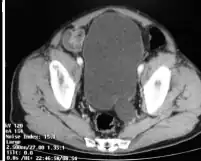

| CT-megaureter close to the bladder | |

Megaureter is a medical anomaly whereby the ureter is abnormally dilated. Congenital megaureter is an uncommon condition which is more common in males, may be bilateral, and is often associated with other congenital anomalies. The cause is thought to be aperistalsis of the distal ureter, leading to dilatation.

The cutoff value for megaureter is when it is wider than 6[1] or 7 mm.[2]